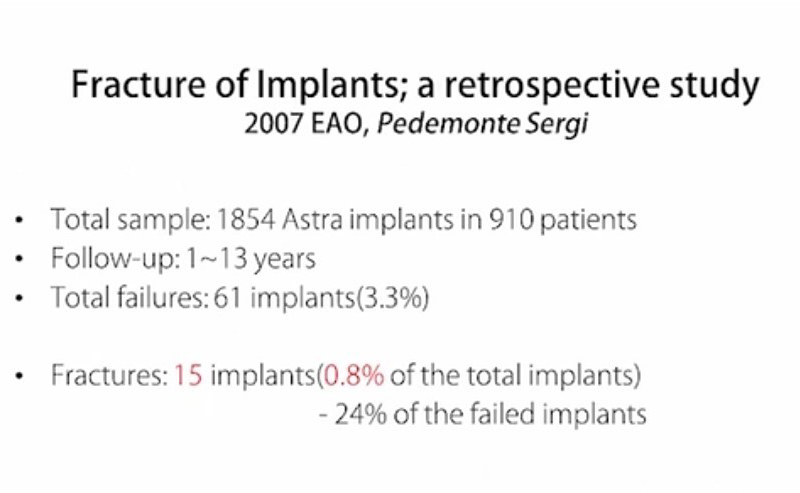

유럽 골융합학회( European Association for

Osseointegration)

대구치부, 특히 7번 싱글은 위험하다. 또한 6번 심을 때 M-D distance(앞-뒤 폭경)가 12mm 쯤 나와서 2개의 픽스쳐는 못 심고 한 개 심어서 해결하는 경우에 특히

조심해야 한다.

픽스쳐도 찢어질 수 있고, 어벗먼트도 부러질 수 있다. 또한 나사 풀림도 많이 발생한다. 이런 특별한 경우에도 EZC와 같은 convertible abutment가 유리하다.